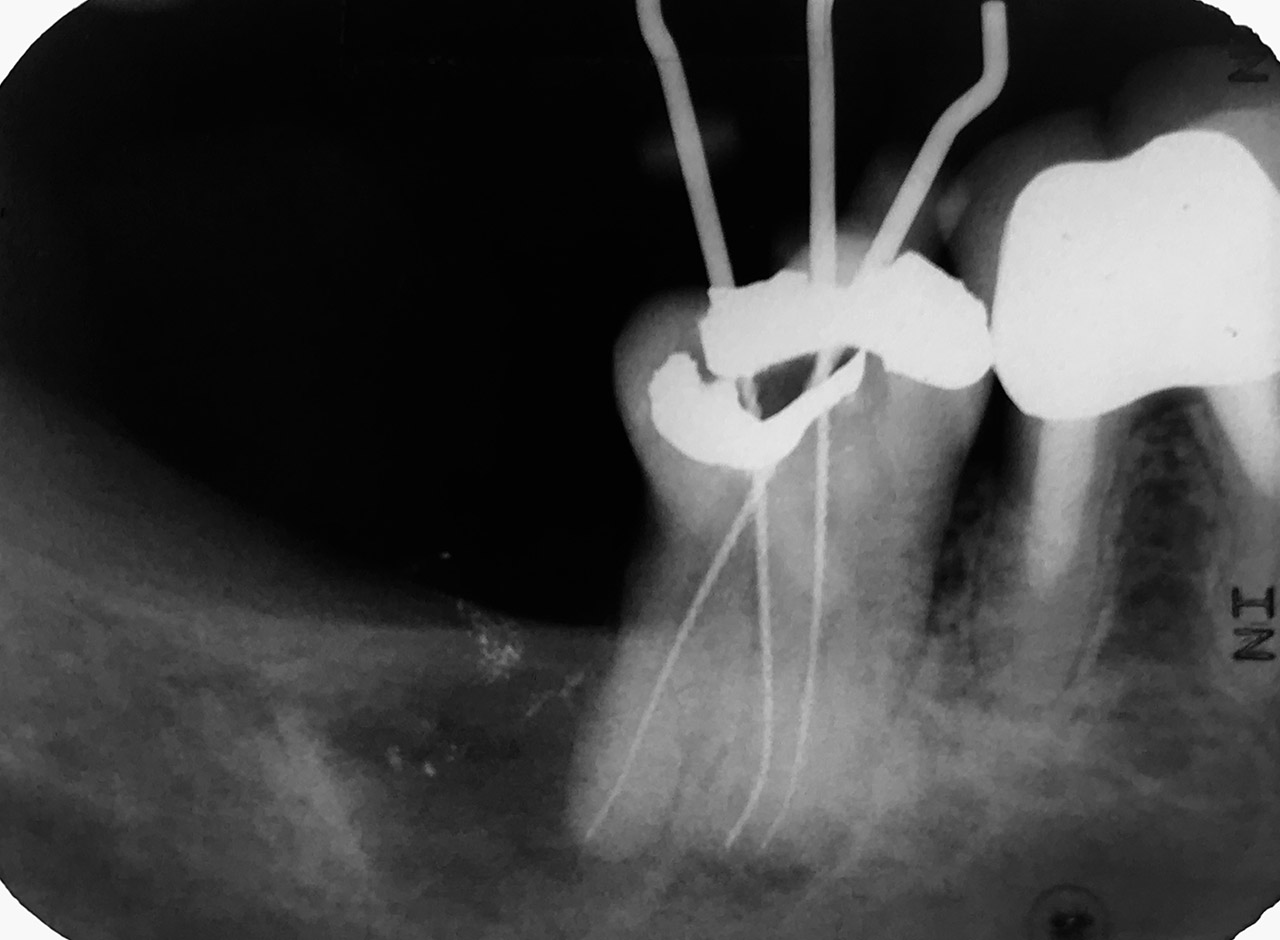

Wurzelbehandlung/Endodontie:

Massiver Paro-/Endodefekt bei den Zähnen 38&37. Extraktion von 38 (Weisheitszahn) und Wurzelbehandlung von 37 (4 Kanäle). Defekt vollständig ausgeheilt.